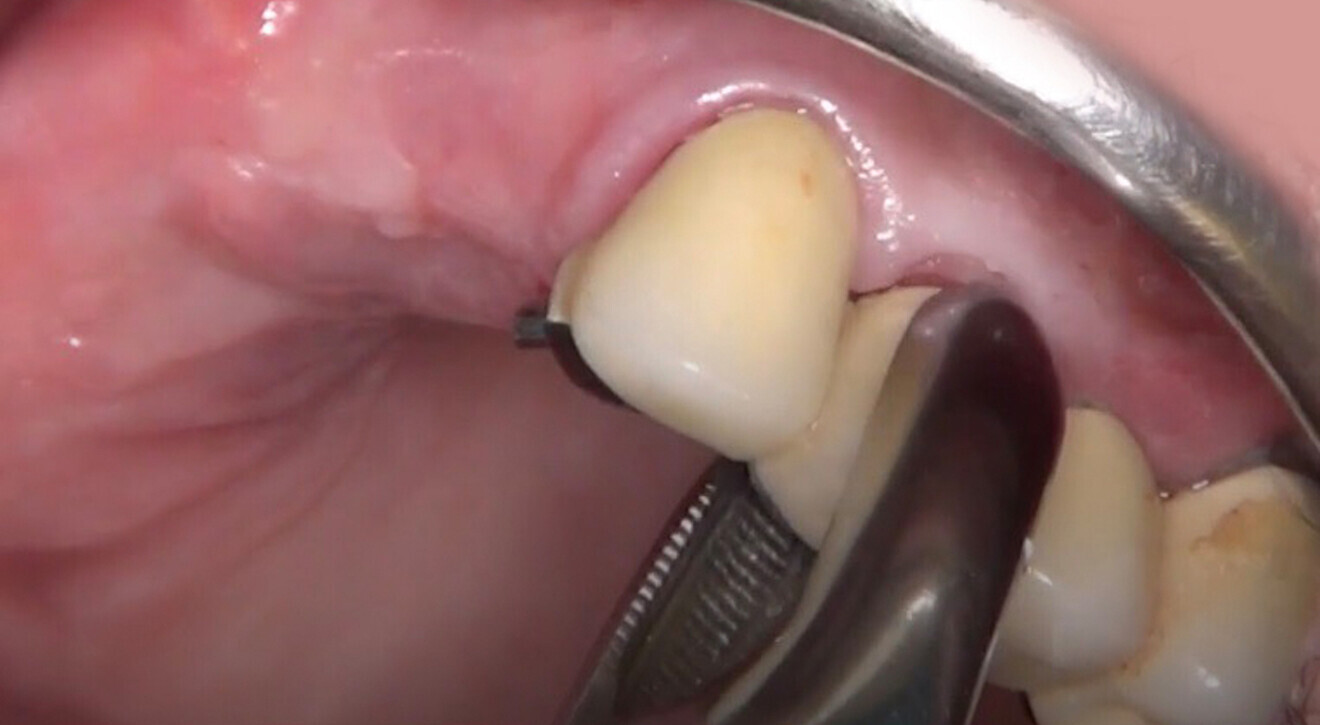

Four months later, we proceeded with the final prosthetic procedure based on clinical and radiographic evidence confirming osseointegration. The case was completed using Straumann RevEX scan bodies for a full monolithic design with a completely digital workflow. First, an intra-oral scan of the opposite arch was taken, followed by an intra-oral scan with the screwed-in temporary abutments. An intra-oral bite scan and an intra-oral scan of the soft tissue with the screw-retained abutments in place were then taken. The reverse scan bodies were attached to the provisional prosthesis, which was scanned extra-orally. Next, the prototype and verification jig were designed, followed by the milling of the prototype and verification jig (Figs. 45 & 46).

During the next visit, the milled prototype and verification jig were tried in, and the design and manufacturing of the final prosthesis were completed (Figs. 47 & 48). The final abutment utilised was Variobase for bridge (Straumann), placed on top of the screw-retained abutments. The material chosen for the final prosthesis was monolithic zirconia (Figs. 49 & 50).

The delivery of the final prosthesis was then performed, and the aesthetics, occlusion and function were verified (Figs. 51–55). The panoramic control radiograph showed that all measurements were within expected ranges (Fig. 56).

At the 18-month follow-up after completing the treatment, an intra-oral, extra-oral and radiographic evaluation were performed. No pathologies were observed, and the results remained stable over time (Figs. 57–62). The patient expressed his satisfaction with the treatment outcomes, stating, “Seeing my new smile before starting the procedure was a game-changer. I was confident from the beginning that my final result would be as I had imagined.”